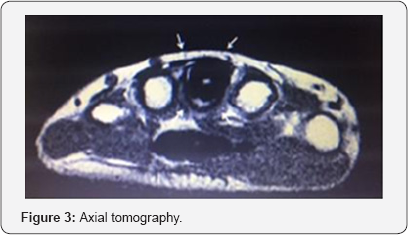

On the simple radiograph, a dense sclerotic lucid radius of bone is present, with bone hypertrophy that completely includes the third metacarpal and invades large bone (Figure 2). Axial tomography shows a dense sclerotic image throughout the perimeter of the third metacarpal (anteroposterior, transverse and caudal skull diameters), associated with large bone edema and its connections with trapezoids and ganchous (Figure 3). In the three-phase bone scan with technetium 99 shows an intense focus of hypercaptation in the carpal and third metacarpal regions (Figure 4). The study by pathological anatomy concludes diagnosis of Osteoid Osteoma (Figure 5).